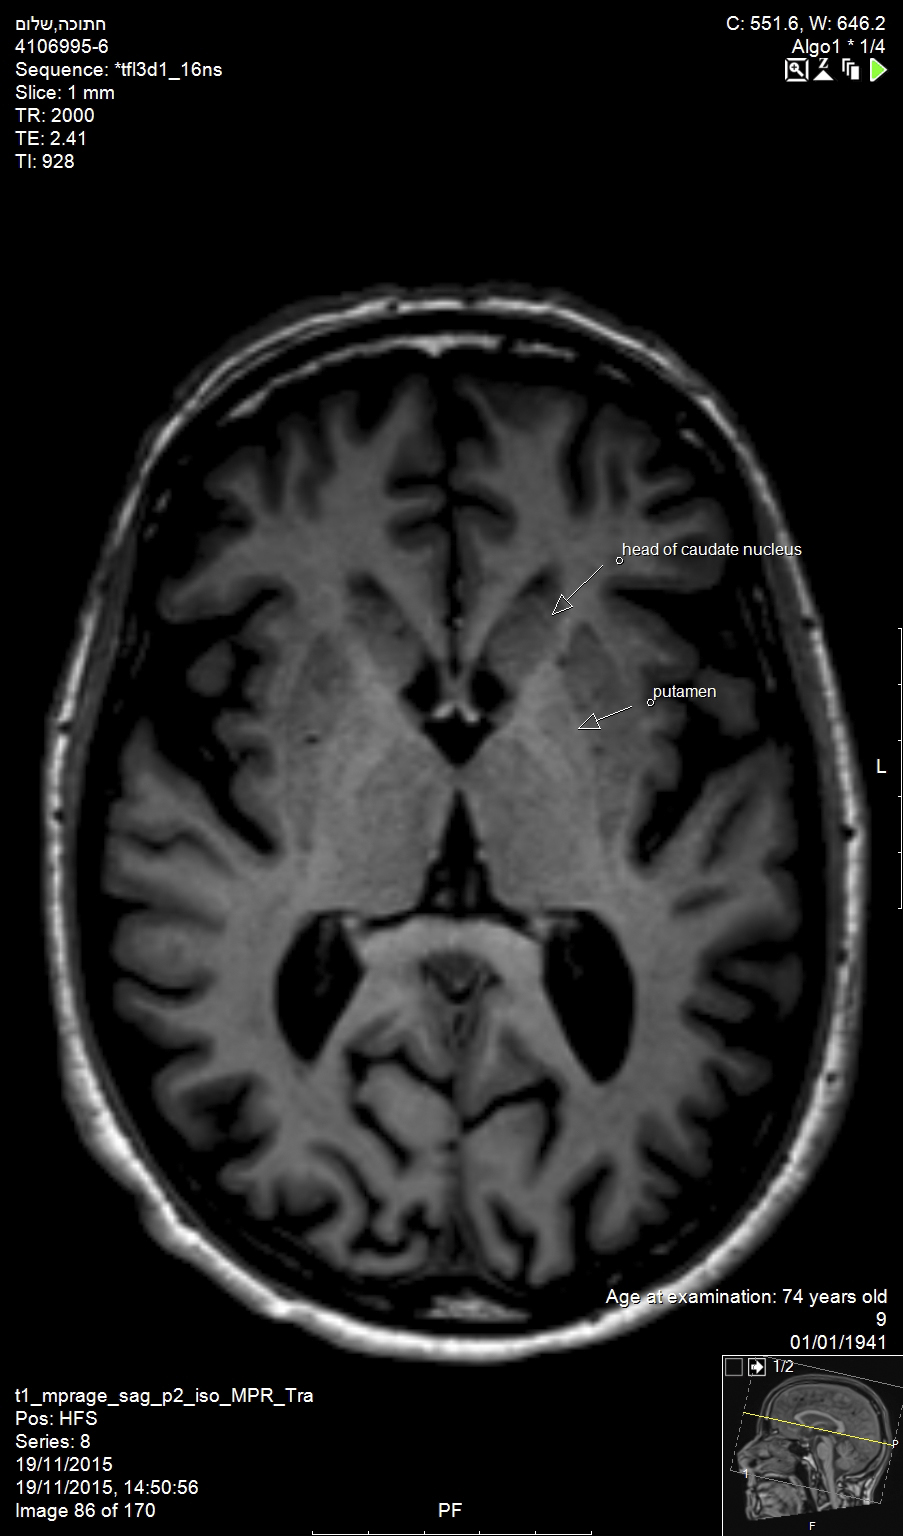

In the brain, Alzheimer’s disease and Huntington’s disease result in widespread loss of neurons (Figure 1), while Parkinson’s disease involves the specific and localized loss of dopaminergic neurons in the substantia nigra. In the brainstem and spinal cord, amyotropic lateral sclerosis and spinal muscular atrophy involve the degeneration and loss of motor neurons. While all of these conditions exhibit unique neuronal pathologies, the exact mechanisms for neuronal loss are complex, making the identification of efficacious treatments elusive.1

Huntington’s disease is named after George Huntington, the physician who described it as hereditary chorea in 1872. It is an incurable, adult-onset, autosomal dominant inherited disorder associated with cell loss within a specific subset of neurons in the basal ganglia and cortex.3 The most striking neuropathology in Huntington’s disease occurs within the neostriatum (Figure 2), in which gross atrophy of the caudate nucleus and putamen (Figure 3) is accompanied by selective neuronal loss and astrogliosis. Marked neuronal loss is also seen in deep layers of the cerebral cortex.4 The clinical features include a movement disorder, cognitive disorder, dementia, and behavior disorder. Patients may present with one or all disorders in varying degrees.5

Fig 1. Alzheimer’s disease and Huntington’s disease result in widespread loss of neurons, as shown in this magnetic resonance image (MRI) of the brain of an elderly patient (top arrow: head of caudate nucleus; bottom arrow: putamen).

Fig 3. Gross atrophy of the caudate nucleus and putamen occurs within the neostriatum in Huntington’s disease (top arrow: head of caudate nucleus; bottom arrow: putamen).